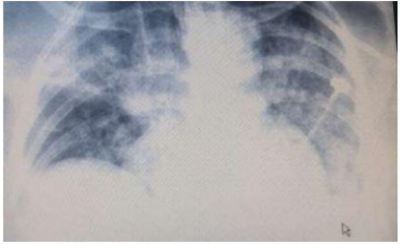

Mulher de 26 anos foi vítima de colisão de motocicleta com automóvel em alta velocidade. Apresent ava contusão pulmonar bilateral e choque hemorrágico, com necessidade de esplenectomia. Não teve lesão intracraniana. Foi extubada no 5o pós-operatório. No 8o pós-operatório, já em programação de alta da unidade de terapia intensiva (UTI), apresentou piora do quadro clínico. Ficou confusa e teve agitação psicomotora grave. Frequência respiratória: 38 incursões por minuto, respirando com uso de musculatura acessória. Gasometria, feita com nebulização de O2 por máscara do tipo Venturi, com fração inspirada de O2 de 50%: saturação de O2: 90%, paO2: 60 mmHg. Pulso: 110 bpm, PA: 90x50 mmHg, tempo de enchimento capilar: 3 segundos, temperatura axilar: 37,9oC. Função renal preservada, com surgimento de leucopenia no hemograma. Ecocardiograma: sem alterações. Com a radiografia ilustrada a seguir, foi fechado o diagnóstico de síndrome da angústia respiratória do adulto (SARA). Qual o grau de SARA, o diagnóstico etiológico mais provável e as condutas apropriadas que devem tomadas?